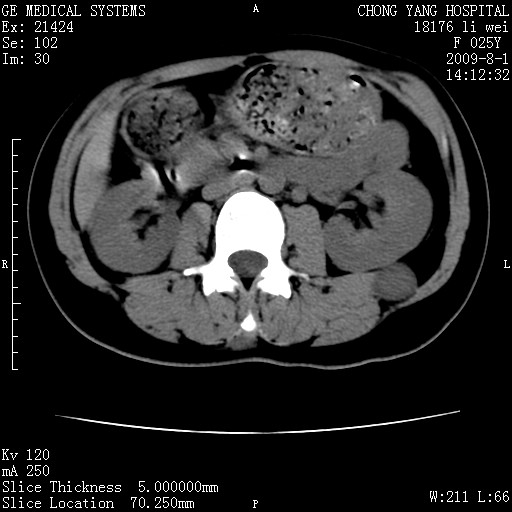

以下是引用pujunzhi在2009-8-1 20:23:00的发言:[br]胸椎旁及背部肌间良性病变,范围广,边界清,沿肌间生长,考虑淋巴管瘤、血管瘤,建议增强扫描。

以下是引用拾荒者在2009-12-30 21:45:00的发言:[br]ct21383:神经纤维瘤病( nf) [br] [br] 神经纤维瘤病。四肢都有,影响美观,四肢上的手术了。[br] [br] [br]谢谢!